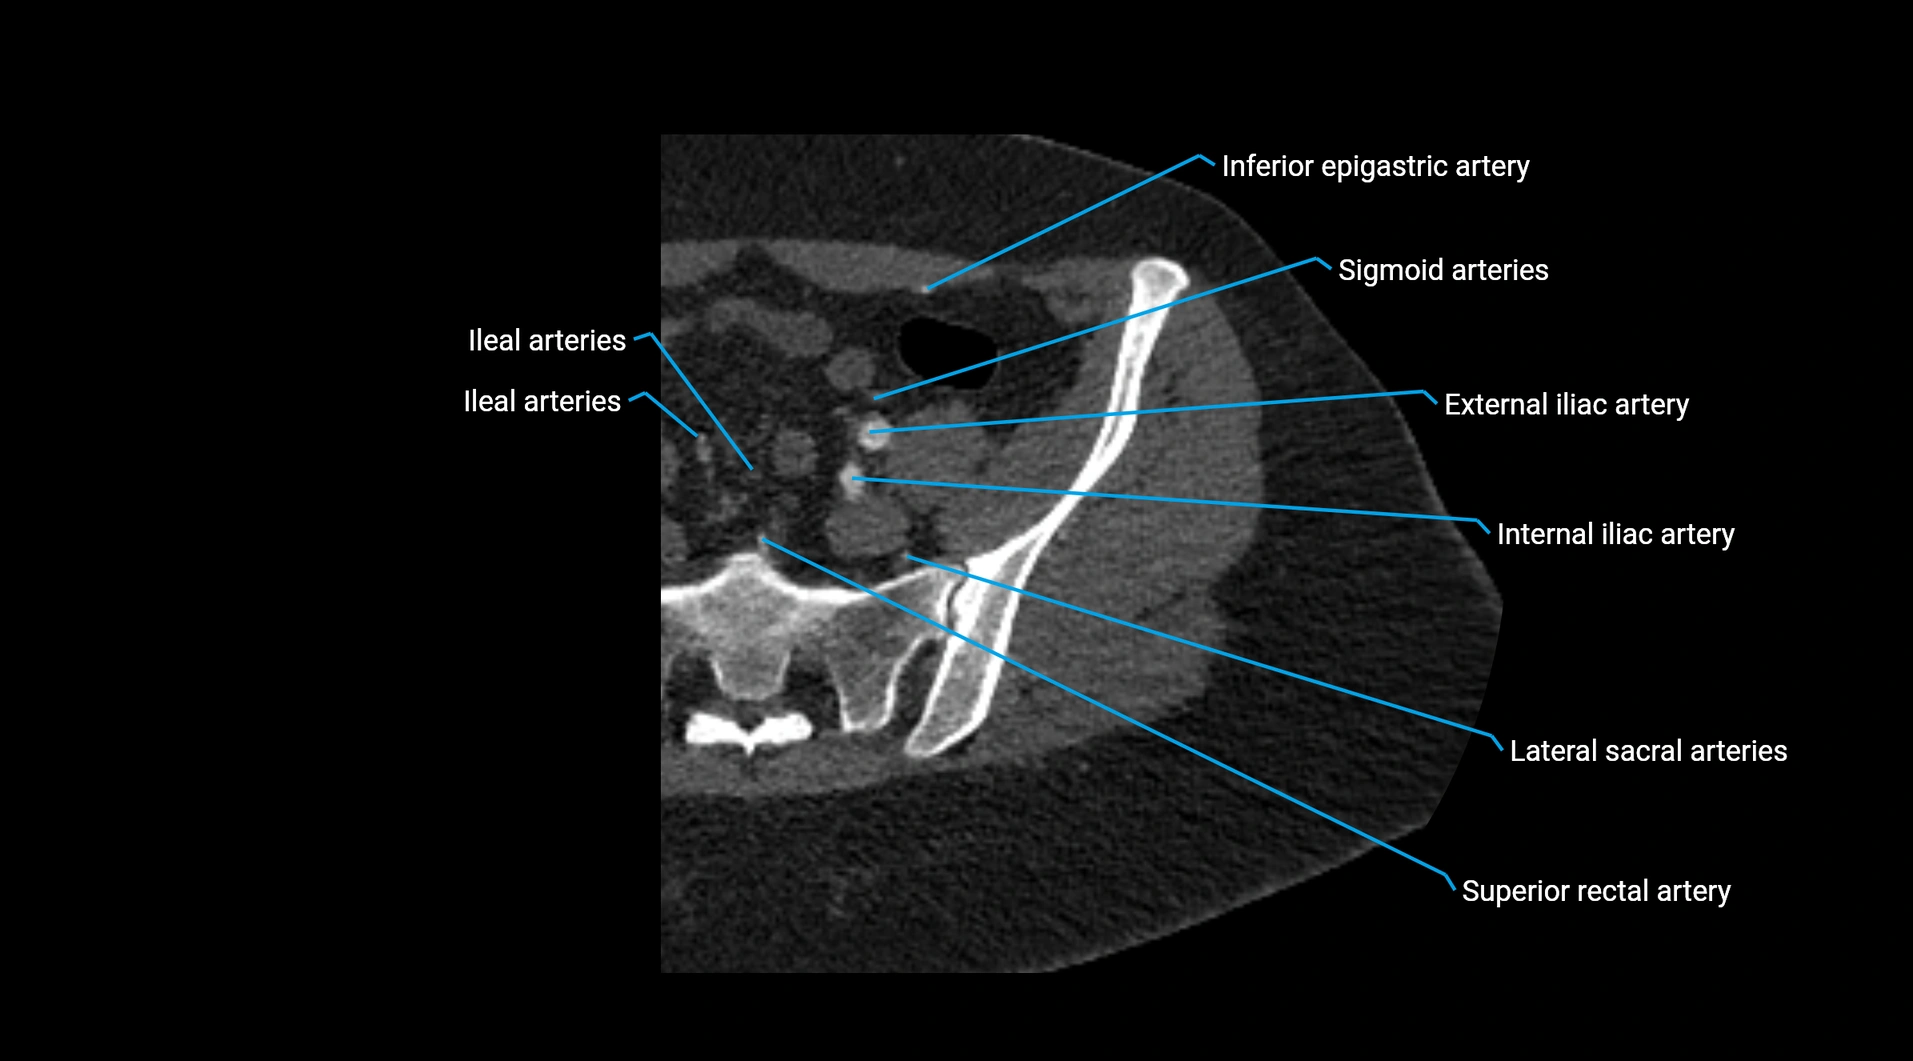

CT images

image